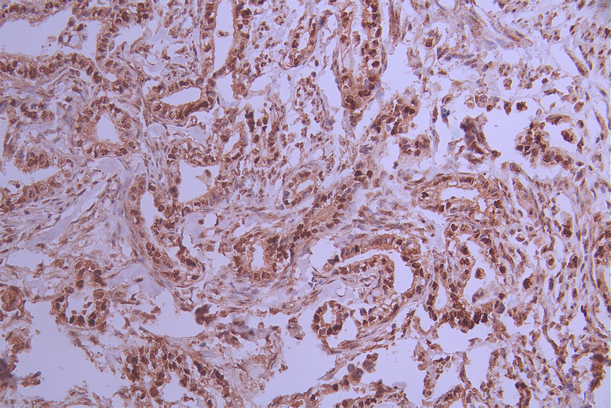

IHC image of CSB-RA586611A0HU diluted at 1:100 and staining in paraffin-embedded human cervical cancer performed on a Leica BondTM system. After dewaxing and hydration, antigen retrieval was mediated by high pressure in a citrate buffer (pH 6.0). Section was blocked with 10% normal goat serum 30min at RT. Then primary antibody (1% BSA) was incubated at 4°C overnight. The primary is detected by a Goat anti-rabbit polymer IgG labeled by HRP and visualized using 0.05% DAB.